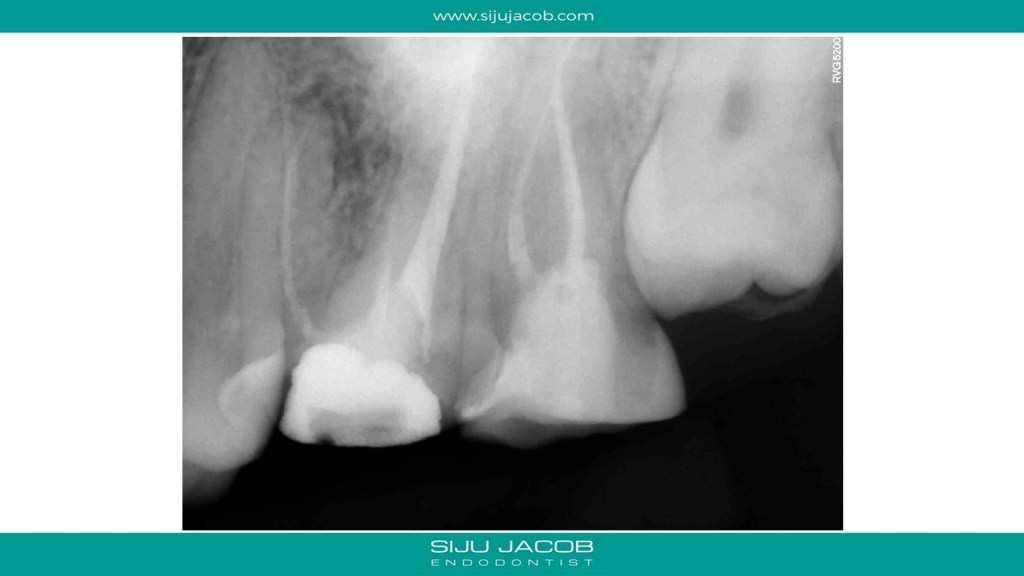

Some cases are such that when you eventually finish, you wonder what the fuss was all about. I struggled to locate the canals in this case. Not sure why. Yes, the access was difficult, but the main reason I struggled was probably the prior access that was made. This made me lose orientation initially. I managed to locate one canal and then took an Inter-appointment CBCT. This made things much easier. More in the short video below:

And below are the clinical slides of the same case: